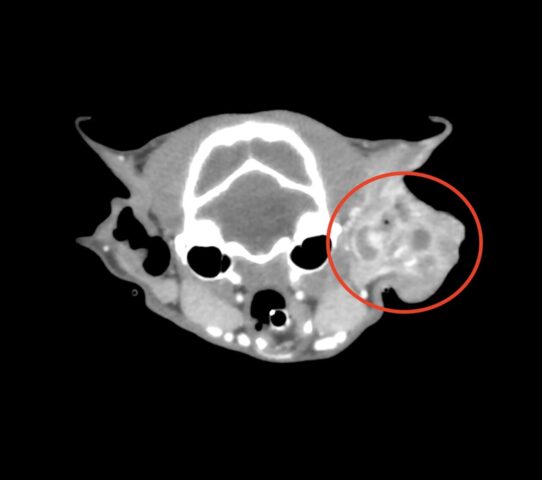

特にCT検査や細胞診検査、病理検査はより専門的な知識が必要です。

当院では、CT検査、細胞診検査、病理検査に特化した各診断医と連携を取り、検査所見を読み取ることで、より適切な診断を下させるよう努めています。

当院では約5秒で動物の全体をスキャンするCTがございます。これにより、動物への麻酔の負担を軽減して、撮影が行えます。また、動物の状態が悪い場合には麻酔をかけずに撮影を行うこともあります。撮影したデータは画像診断医“によって”正確な診断を行っております。動物のがんを早期に発見してあげることが何よりも動物に健康でいてもらえることに繋がりますので定期的な健診にも当院へお越しください。